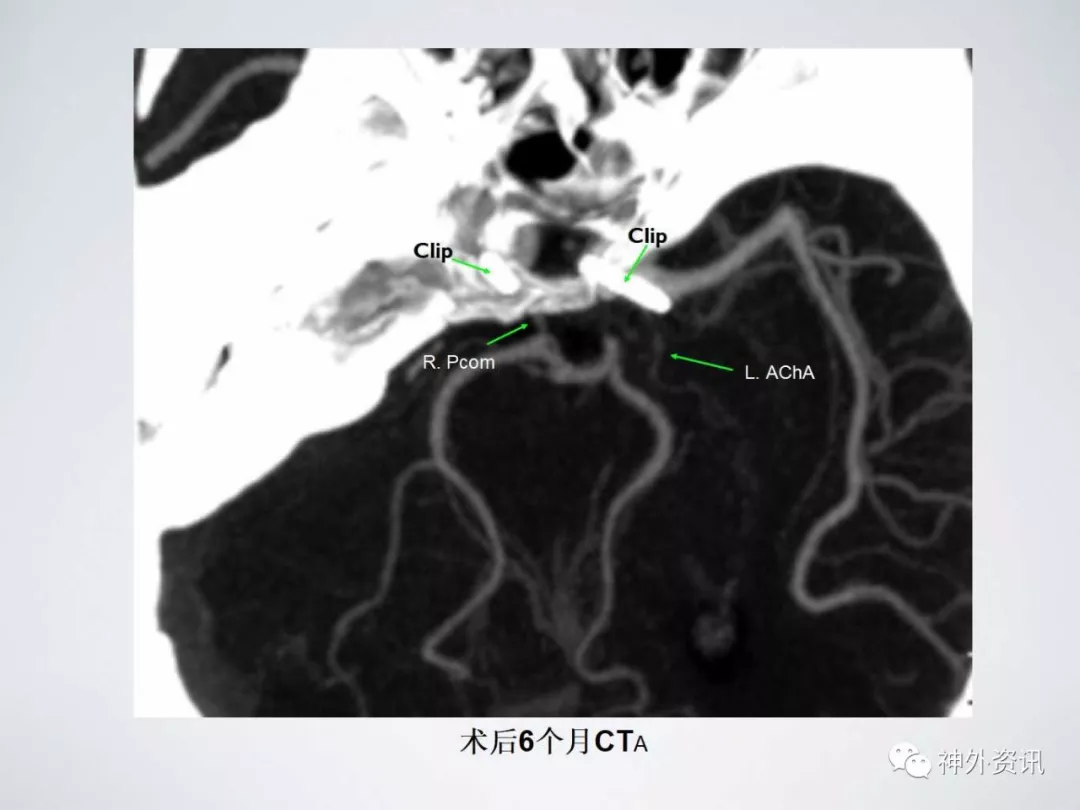

术后6个月

相关研究表明,对于MIA来说,介入治疗与开颅夹闭治疗的术后并发症并无统计学差异,但是开颅夹闭治疗的复发率更低。由于MIA空间分布的特殊性以及解剖结构的复杂性,一次性夹闭治愈MIA手术风险高、技术难度大,一直困扰着神经外科临床医师。但是随着手术器材和显微技术的进步,吴建梁教授的团队不断探索,制定了一系列的术前评估、术中操作及术后管理的质控标准。截止目前,吴建梁教授团队已开展了两百多例由单侧入路夹闭颅内多发动脉瘤病例的手术治疗,并且经过专项影像学和认知功能测评和随访,其与同期单发动脉瘤夹闭手术相比无统计学差异,是一种安全有效的治疗策略。

因此对于颅内多发动脉瘤患者,尤其是双侧颅内多发动脉瘤的病例,通过综合评估可行单侧开颅夹闭的应积极手术治疗,这样既可以减少患者再次手术的痛苦及治疗时间,又能节省患者住院费用,从而使患者获得最大的收益。